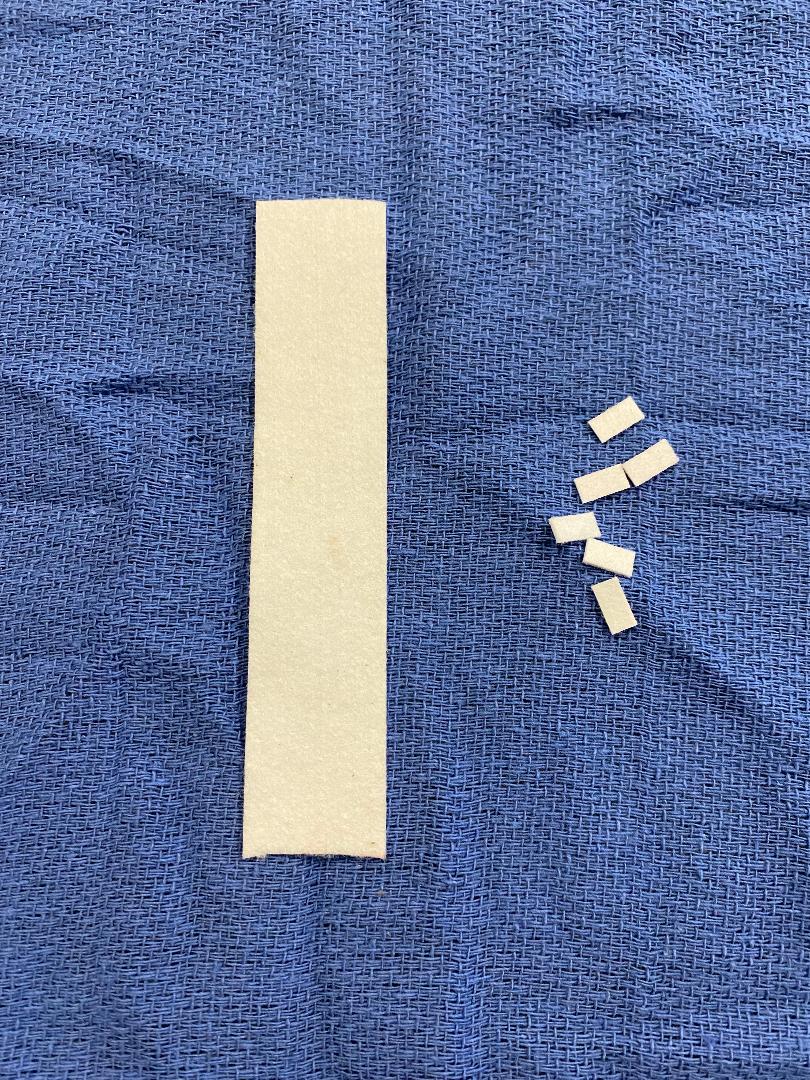

There are various sizes of pledgets. The smaller, harder ones seen below are generally for cardiovascular use (in fact, most pledgets are used in cardiac or vascular cases).

In general surgery, we usually use the larger pledgets that you have to cut to the size you want.